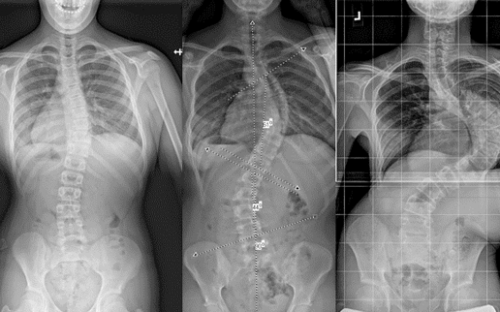

اعوجاج العمود الفقري عند الأطفال والمراهقين هو من أكثر المشكلات التي تثير قلق الأهالي، خصوصًا عندما يخبرهم الطبيب أن الانحناء قد يزداد مع الوقت إذا لم تتم متابعته أو علاجه بالشكل الصحيح. ولهذا يبحث الكثير من الأهالي عن إجابة واضحة لسؤال مهم: ما الذي يمكن أن يجعل اعوجاج العمود الفقري يسوء؟

السبب الرئيسي لزيادة الانحناء هو النمو السريع. فعندما يدخل الطفل أو المراهق مرحلة النمو، خصوصًا بين عمر 10 و15 سنة، يبدأ العمود الفقري في التمدد بسرعة، وهنا يمكن أن يتفاقم الانحناء إذا لم تتم المتابعة الصحيحة.

إجراء أشعة متابعة بانتظام لمراقبة زاوية الانحناء (زاوية كوب).